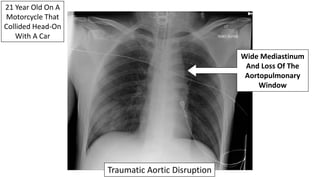

21 Year Old On A

Motorcycle That

Collided Head-On

With A Car

Wide Mediastinum

And Loss Of The

Aortopulmonary

Window

Traumatic Aortic Disruption